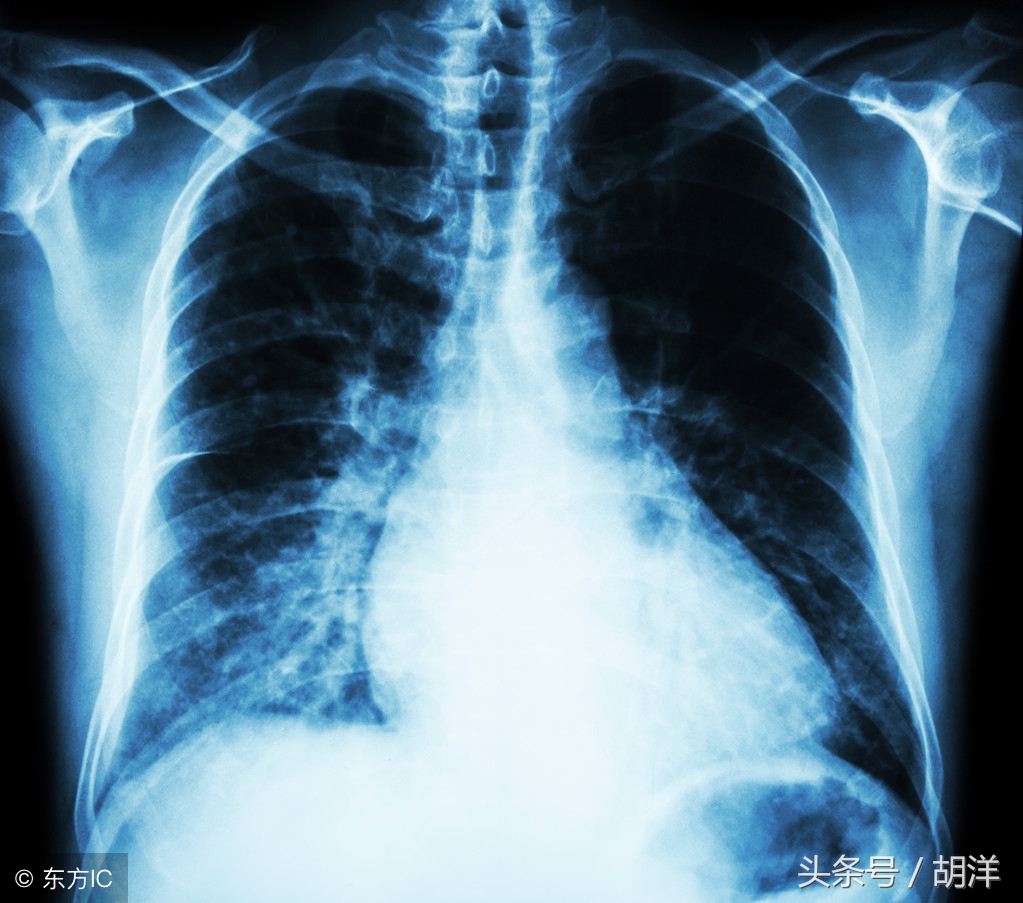

小细胞肺癌在所有肺癌病人中占15-20%,恶性程度高,容易通过血液和淋巴道转移,转移发生早而且广泛。由于小细胞肺癌与其他肺癌有完全不同的特性,因此分期方法有所不同,除了TNM分期,常用美国退伍军人分期标准,分为局限期和广泛期。局限期小细胞肺癌的特点是肿瘤局限于一侧胸腔内,包括有锁骨上或前斜角肌淋巴结转移和同侧胸腔积液。当病变超出局限期范围,均称为广泛期。